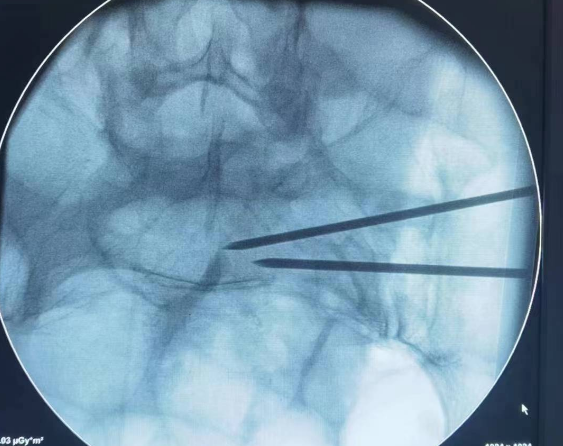

李东柱副主任医师带领付开封,郭强医师立即制定详细手术方案,在麻醉科配合下,应用骨科机器人行骨盆后环第1、2骶髂关节螺钉固定+前环Infix内固定,手术顺利,术后护理团队精心照护,手术成功,尽最大努力实现了骨盆完美复位及精准螺钉置入、固定。

任志勇专家总结:骨盆骨折在临床中非常常见,通常合并胸部损伤、脊柱骨折,有些甚至合并血管损伤、神经损伤,一旦发生后,需要及时就诊于医院,此种损伤通常需要高超的技术和丰富的临床经验,做出对患者最好的手术治疗方案,通过各个科室配合,尽快的进行和完成手术,越早进行手术效果越好,骨科机器人手术实现了精准和快速手术,一方面可以通过精准手术使螺钉置入更加准确并坚强固定,避免了神经、血管损伤风险,然后通过机器人手术可以避免反复穿刺和透视,减少了副损伤、手术时间和辐射,术后康复同样重要,通过后期积极康复,取得一个较好的临床效果,希望大家以后注意安全,一定避免类似损伤,一旦发生类似情况,请及时就医。